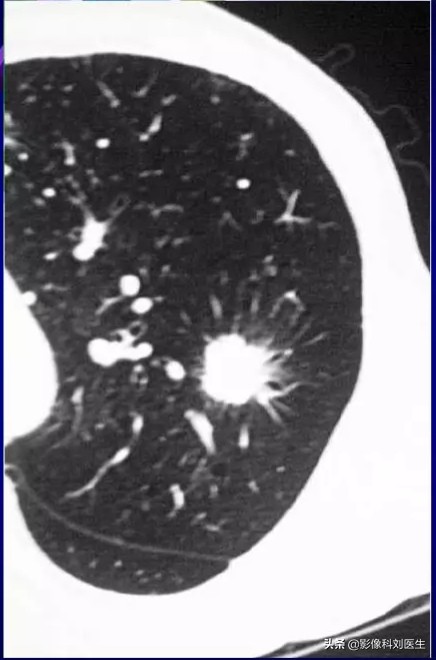

2. 形态欠规则结节。

病灶表现为数个结节堆聚,这是由于癌组织以一个中心向周围多个腺泡浸润生长所形成的,由于其生长不均衡,中间有残余肺泡组织,即形成所谓小泡征。肿块生长的同时遇有血管或支气管的阻碍形成切迹,即所谓分叶。

3. 边缘欠光滑。

主要表现为棘状突起和短毛刺,毛刺往往较密集,周边均有分布,两者是由于侵及肺泡表面或小叶间隔及淋巴管形成的;有别于炎症性肿块的边缘毛刺,炎症性毛刺表现较长和稀疏,一般只有二、三条,它是由于炎症慢性过程中,纤维化所致。